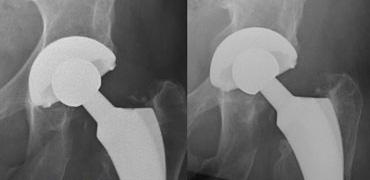

LEFT: Revision THA with a large femoral stem with periprosthetic fracture.RIGHT: Cement extrusion intrapelvic through acetabular defect.

Gãy xương quanh khớp nhân tạo

Gãy xương có thể xảy ra sau phẫu thuật ở những bệnh nhân có chất lượng xương kém và sử dụng khớp nhân tạo thay thế có cán dài, hoặc khi giải phẫu bất thường như trong trường hợp loạn sản khớp háng hoặc đã từng phẫu thuật trước đó.

Gãy xương cũng phổ biến hơn với các cán xương đùi không xi măng, vì các loại này phải vừa khít chính xác và có thể gây gãy xương trong quá trình đặt khớp.

Tỷ lệ gãy xương dao động từ 0,1 đến 1,0 phần trăm đối với các thành phần có xi măng và từ 3 đến 18 phần trăm đối với các thành phần không xi măng. Hầu hết các trường hợp gãy xương trong phẫu thuật xảy ra ở phía xương đùi.

Tràn xi măng ra ngoài

Khi ổ cối được chuẩn bị để đặt cốc, có thể xảy ra thủng. Khiếm khuyết này được lấp đầy bằng mảnh xương, xi măng hoặc ghép xương.

Tràn xi măng ra ngoài thường không có triệu chứng.

Các biến chứng hiếm gặp bao gồm rò ruột, bao bọc các cấu trúc mạch máu thần kinh và bỏng thành bàng quang.